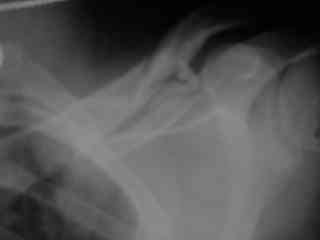

Справа перелом практически поперечный, можно попробовать интрамедуллярно стержнем. Личного опыта правда не имею, у нас стандартом при оперативном лечении переломов ключицы является тот же остеосинтез пластиной. Но в литературе описана методика даже закрытого остеосинтеза - так, в порядке обсуждения.

Bolnogo operirovali plastinami, snimky zdes'.

CIMG1145.JPG

Похоже, все прошло по плану. Поздравляю с успешной операцией!

Pneumatorax hirurg punctiroval i lechil dalshe, operasia zanimala 1 chas 35 minut, ni bilo problem ossobih.